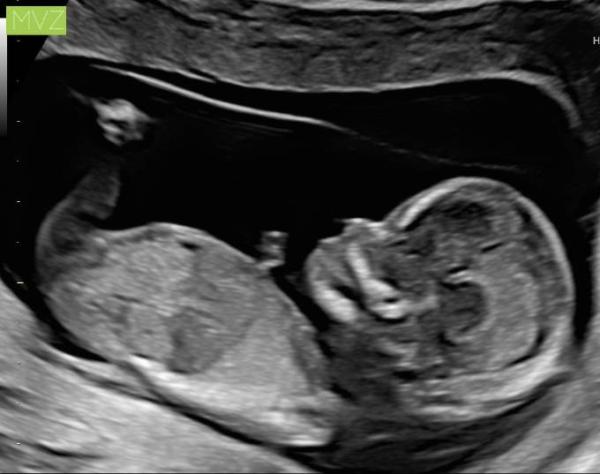

Hi, ich war gestern Abend zur Nackenfaltenmessung. Es war alles super, keinerlei Anzeichen für Fehlbildungen oder genetische Defekte. Ich wurde von dem Arzt allerdings eine Woche vordatiert, da der kleine Wurm schon sehr groß ist. In der letzten Vorsorge bei meinem Gyn kam schon die Anmerkung dass ich evtl schon etwas weiter sei aber eigentlich kann das nicht sein Wir sind auf jeden Fall überglücklich das alles gut ist Ach ja und es wird zu 80% ein Mädchen Ich hoffe es geht allen soweit gut? Liebe Grüße

Bild zu Nackenfaltenmessung und Outing - Forum für Juni - Mamis